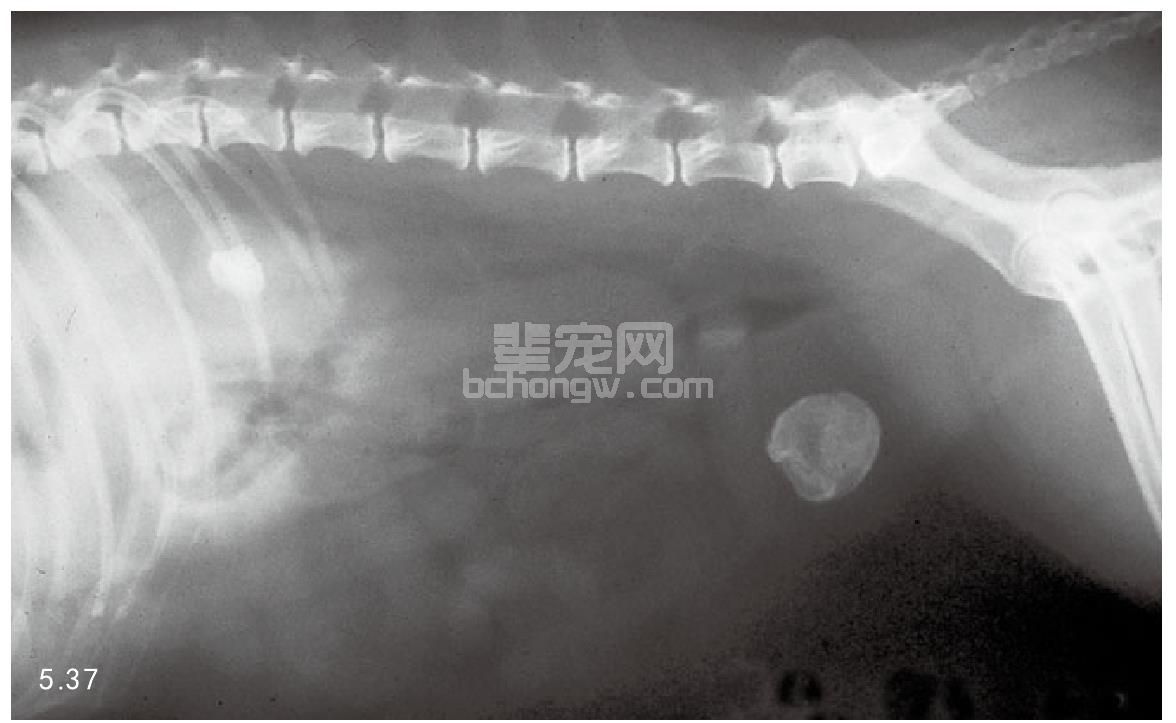

图5.37和图5.38 尿结石影像:图5.37犬膀胱鸟粪石结石的X线片。图5.38超声检查猫的固体性尿结石。

诊断 尽管临床表现可以提示结石的大体位置,但是对于泌尿道结石及其数量、大小和位置一般使用X线和超声波检查来确诊(图5.37和图5.38)。使用X线、造影,包括静脉肾盂造影、膀胱造影和逆行性尿道造影来诊断(图5.39)。